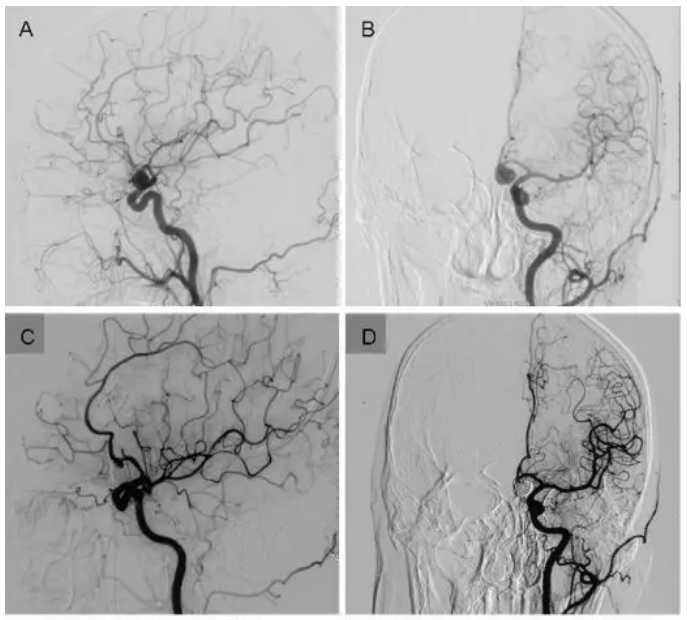

图三:如图是上述病人的术中所见。在术中可见动脉瘤内的填充物向外突出,且视交叉被填充物压迫(A-C);完全显露并阻断动脉瘤近端和远端血管后,我们将填充物和周围粘连组织分离,然后取出(D-F);然后通过调整动脉瘤内剩下填充物的位置,使瘤颈充分暴露,制造夹闭空间(G);夹闭瘤颈后,再将剩余的动脉瘤内填充物取出,并在第一个夹子后再上一个动脉瘤夹以保证动脉瘤被完全夹闭(H-I)。